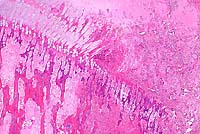

- Microscopically, necrosis and fibrinopurulent debris

are prominent at the level of the distal growth plate of the

metacarpal bone. Mature and fragmented neutrophils are common,

fibrin thrombi are present in small blood vessels, and there

is widespread necrosis of cartilaginous, osseous, and myeloid

elements. Lesions extend into the epiphysis and diaphysis, and

occasional clefts are present in the growth plate cartilage.

The necrotic areas are poorly circumscribed by mononuclear leukocytes

and dense fibrovascular stroma. Microscopic findings in other

tissues included histiocytic foci (paratyphoid nodules) in the

liver and crypt abscesses in the ileum.

4x

obj

- Case 20-1. Bone. At the margin of the necrotic sequestra

(left), which extends through the growth plate, there is a mixture

of degenerate neutrophils, fibrin, edema, and cell debris (right).